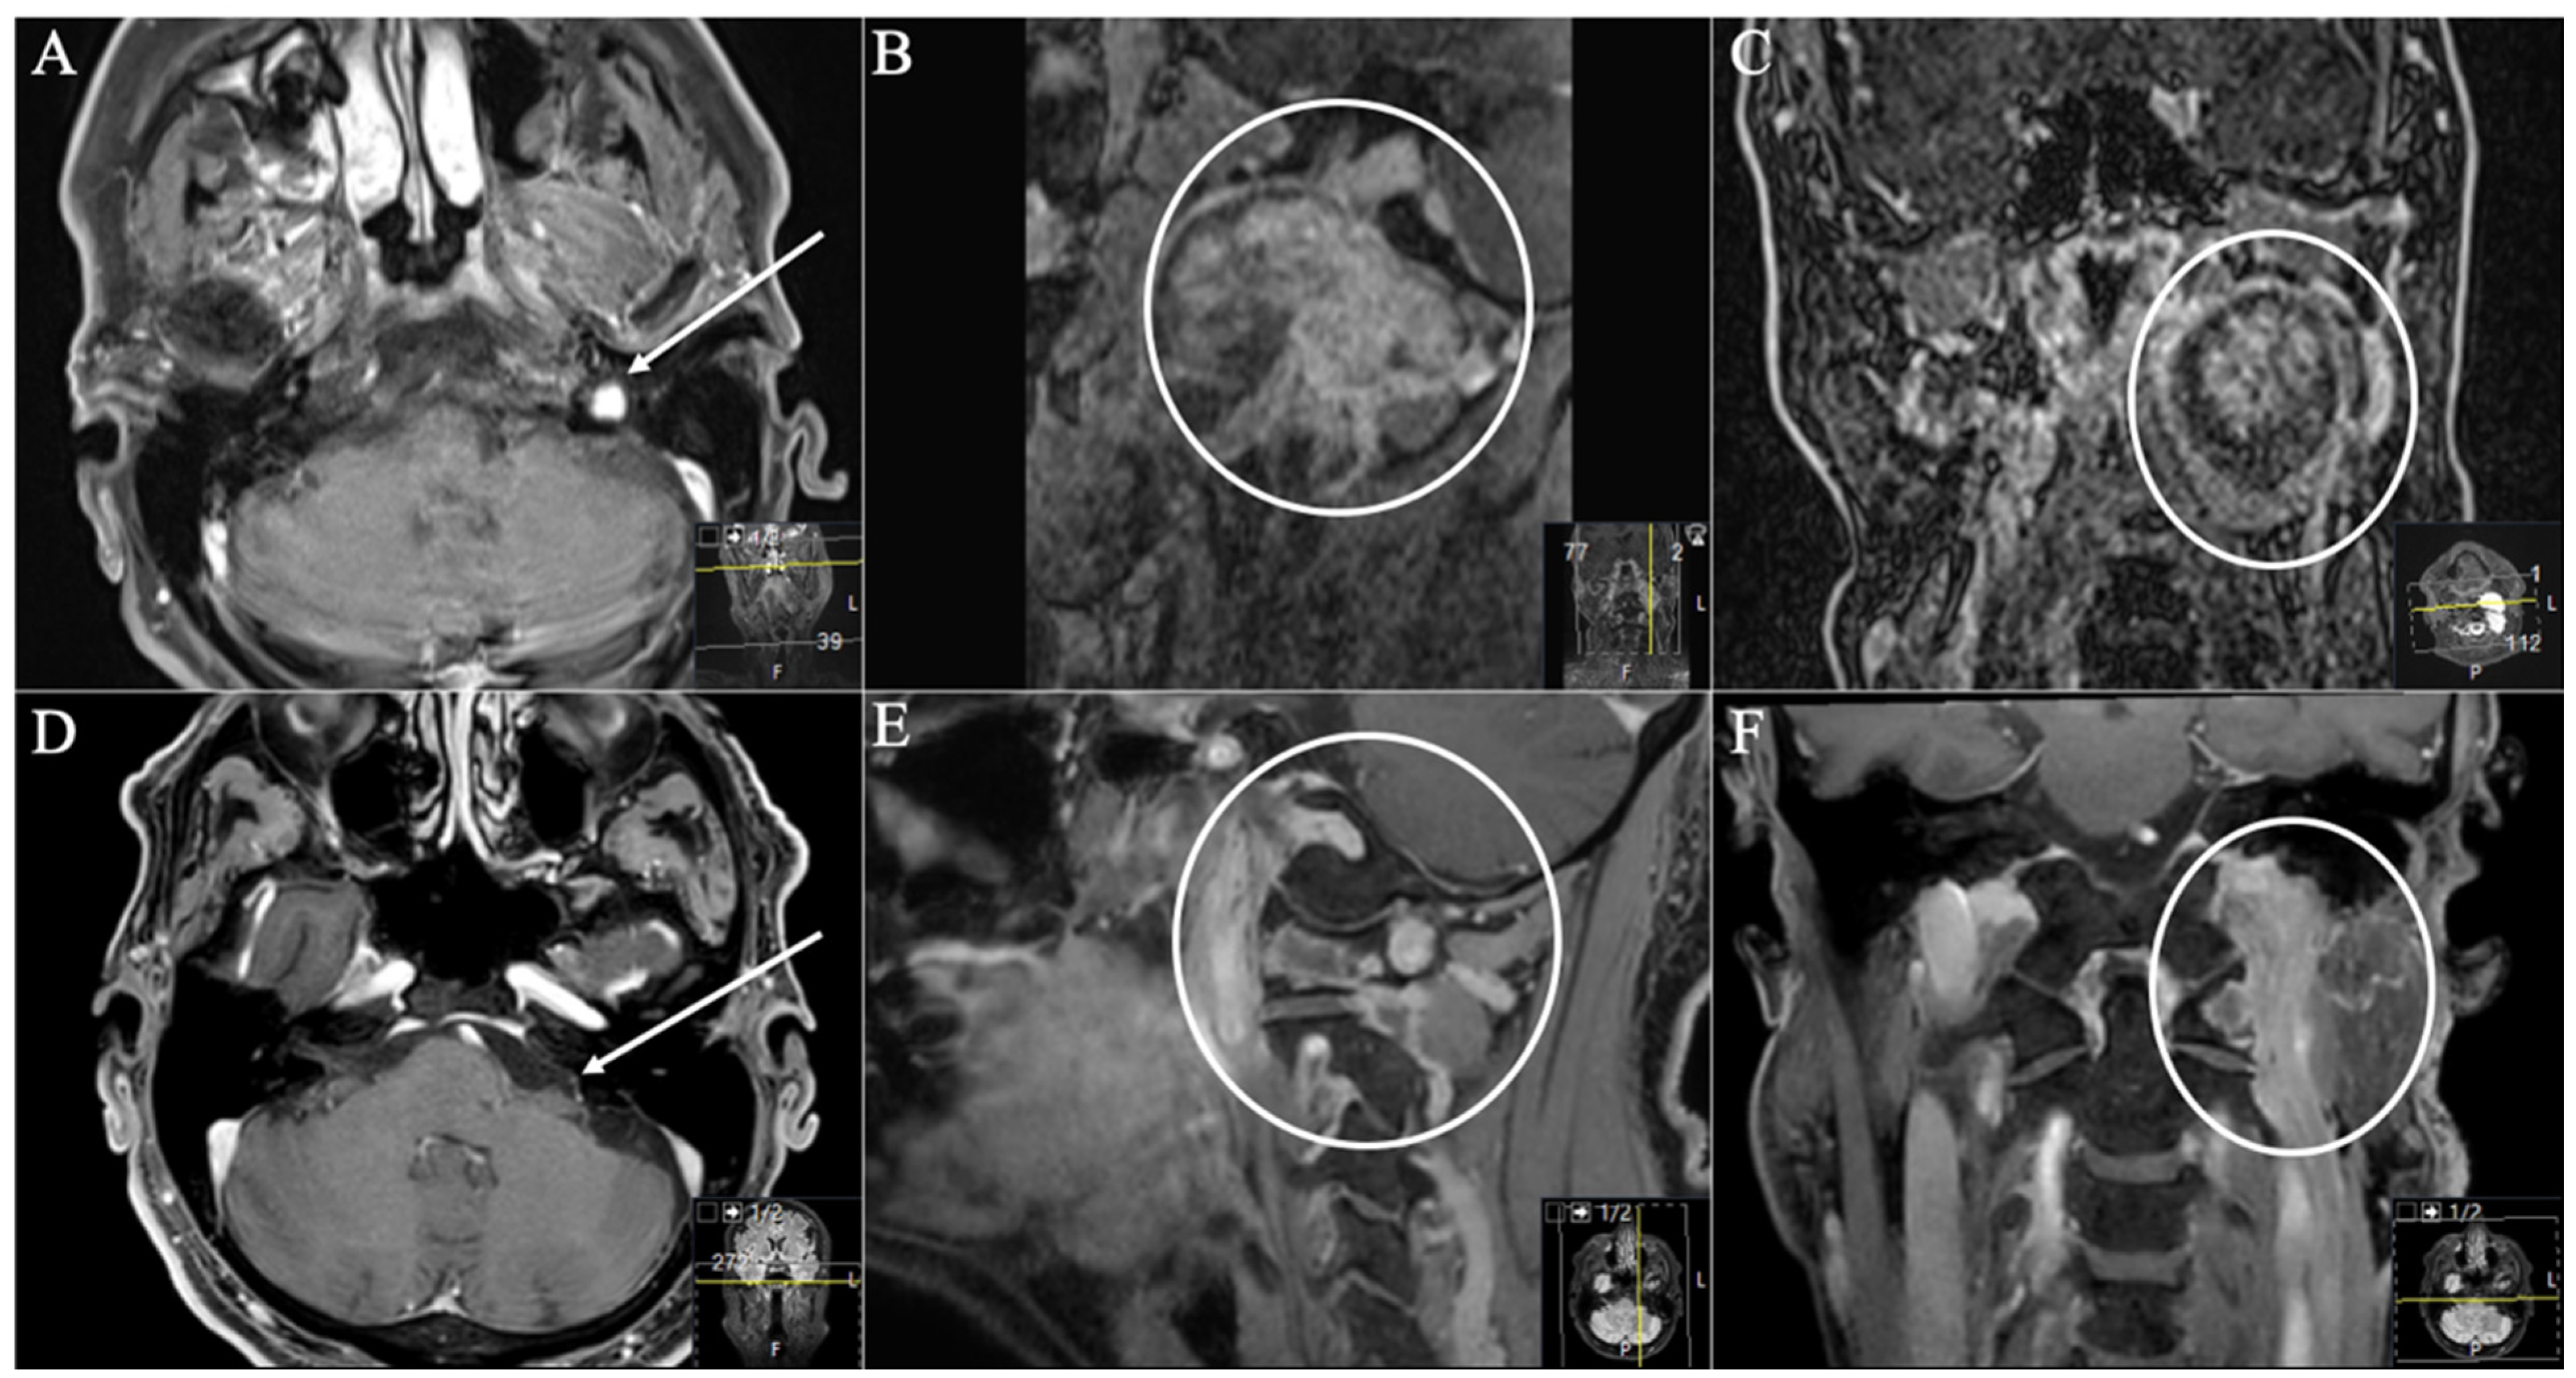

2.3. Surgical Approaches

2.3.1. Retrosigmoid Approach

2.3.2. Extreme Lateral Infrajugular Transcondylar (ELITE) Approach